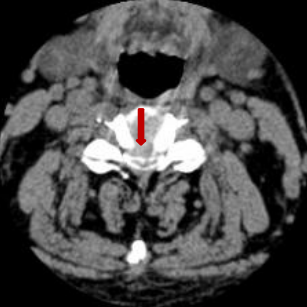

术前脊髓造影后颈椎CT。

颈椎间盘突出明显。